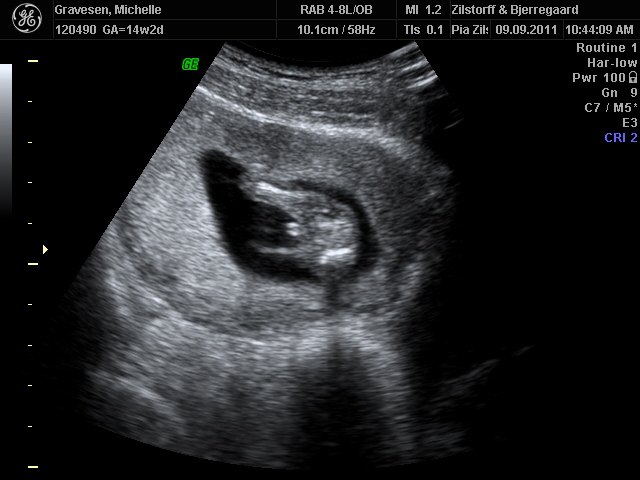

Dreng eller pige?? hvad tror i?

Billederne er fra kønsscanning i fredags hvor vi ikke kunne få klart svar så skal afsted igen på fredag.

hun var 14+2 den dag hun blev scannet

På øverste billede ligner det en tap.... Mit scanningsbillede med Frederikke så ihvert fald anderledes ud.

Jeg ville gætte på en dreng .. Hvis det havde været en pige havde der været to hvide streger og det er der ikke